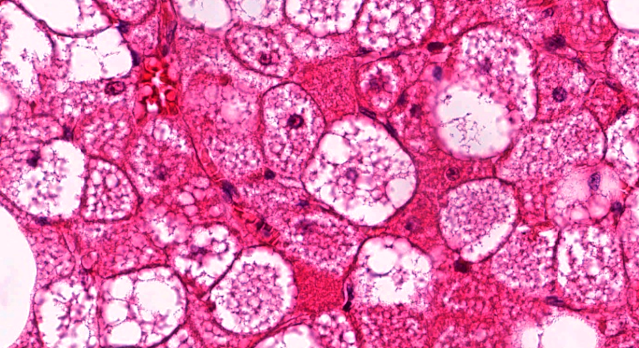

Dermatopathology Case 224 Get link Facebook X Pinterest Email Other Apps June 01, 2022 A 35 year old man presented with a slow-growing mass on the back. Answer Get link Facebook X Pinterest Email Other Apps Comments